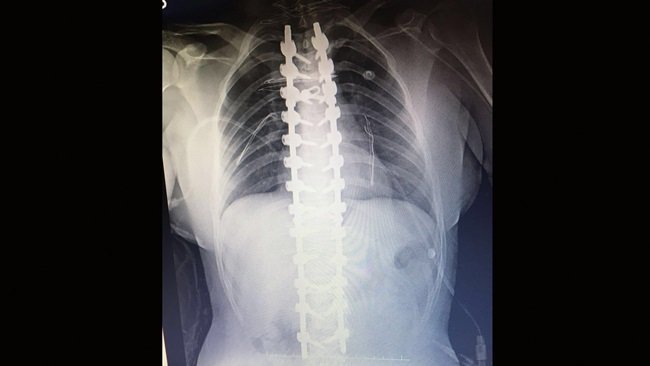

Kdz. Ereğli Devlet Hastanesi Yöneticisi Opr. Dr. Muharrem Erdem, ameliyatı gerçekleştiren Beyin Cerrahı Uzmanı Opr. Dr. Mustafa Kaya ve ekibine teşekkür ederken, Ereğli ve bölgesindeki hastaların artık bu tür ameliyatlar için büyük şehirlere gitmesine gerek kalmadığını söyledi. Erdem, omurganın düzeltilmesi sırasında 26 adet vida, 2 rot ve 2 ara bağlantı plağı konularak yapıldığını anlattı.

Ameliyat 5.5 saat sürdü

17 yaşındaki genç kızın ameliyatını yaparak yeniden sağlığına kavuşmasını sağlayan Kdz. Ereğli Devlet Hastanesi Beyin Cerrahi Uzmanı Opr. Dr. Mustafa Kaya, 5.5 saat süren ameliyat ile boyundan kuyruk sokumuna kadar olan şekil bozukluğunu giderdiklerini ifade etti. Opr. Dr. Kaya “Hastamızın bütün şekil bozukluğunu normal insanlardaki şekline dönüştürdük. Herhangi bir nörolojik defisit gelişmeden hastamızı bir hafta sonra sosyal hayatını idame edecek şekilde taburcu ettik. Hastamız bize geldiğinde cerrahi sınırlardaydı. Öğrenci olduğu için ameliyatı için okulların tatil olmasını bekledik” dedi.

KDZ. EREĞLİ DEVLET HASTANESİ DOKTORLARIN BEYİN CERRAHİ UZMANI MUSTAFA KAYA, GENÇ KIZIN OMURGASININ 5,5 SAAT SÜREN AMELİYAT İLE DÜZLEŞTİRİLEREK SAĞLIĞINA KAVUŞTURULDUĞUNU SÖYLEDİ. (VEDAT KILIÇ/ZONGULDAK-İHA)

KDZ. EREĞLİ DEVLET HASTANESİ DOKTORLARIN BEYİN CERRAHİ UZMANI MUSTAFA KAYA, GENÇ KIZIN OMURGASININ 5,5 SAAT SÜREN AMELİYAT İLE DÜZLEŞTİRİLEREK SAĞLIĞINA KAVUŞTURULDUĞUNU SÖYLEDİ